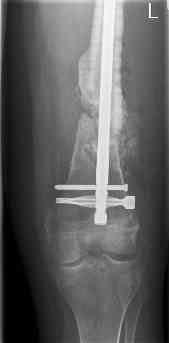

16 yr old boy, high energy motorcycle trauma trauma in July 2005 with:

- hip dislocation + acetabular fracture L

- distal femoral fracture L

- tibial shaft fracture L

- metatarsal fractures L

july 05: LISS femur, LCP plate tibia, double recon. plate post. acetabulum

oct 05: cancellous bone graft femur

aug 06: blade plate + bone graft

nov 06: revision blade plate

feb 07: retrograde nail + bone graft + BMP

may 07: dynamisation nail

sept 07: locking screw removal (max. dynamisation reached)

nov 07: persistant non-union distal femur; other fractures healed uneventfully.

All with gradual/partial weightbearing etc. Currently 50-100% weight bearing, no pain.

Soft tissues are intact. No smoking or diabetes.CRP <2